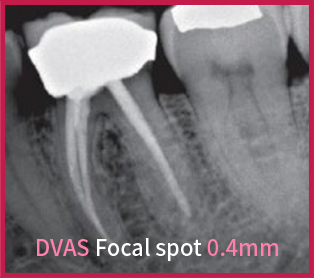

0.4㎜'s Focal Spot gives very clear image to the dentists